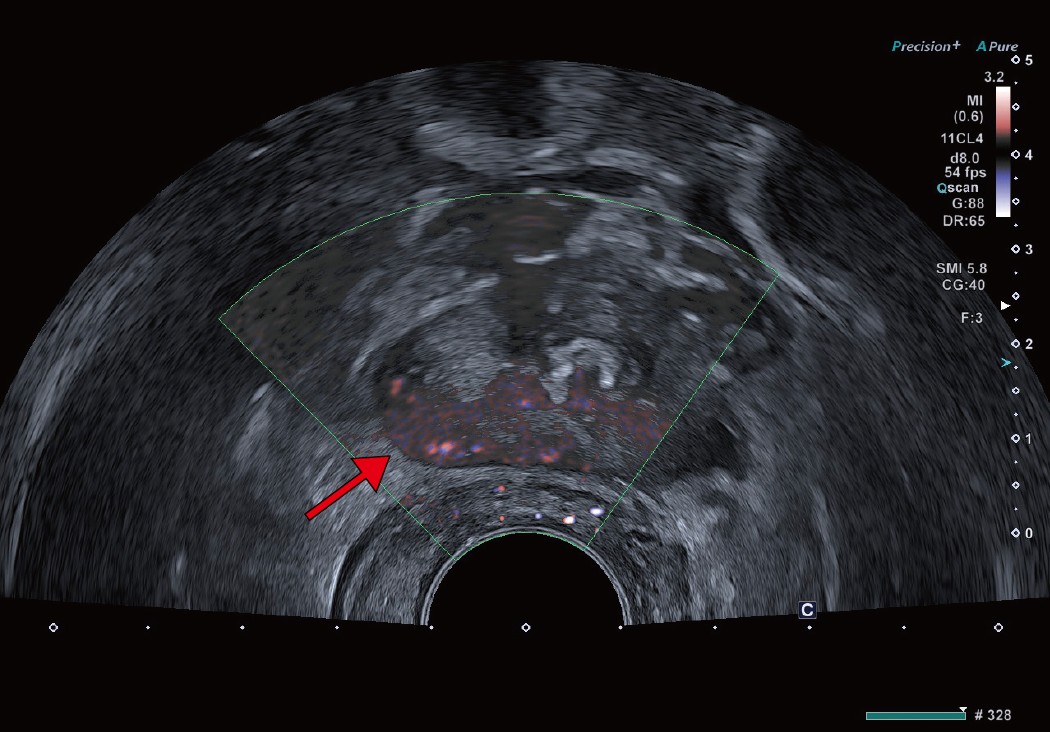

Aplio meによる臨床画像 症例:前立腺がんに対する経直腸エコーによる針生検

a:経直腸超音波画像。前立腺右葉辺縁領域に低エコー領域を認めるが、がんとは断定しづらい。 a:経直腸超音波画像。前立腺右葉辺縁領域に低エコー領域を認めるが、がんとは断定しづらい。

b:前立腺右葉辺縁領域に明らかなSMI陽性像、すなわち微小血管が描出されており、同部位からGS4+4が検出されている。 b:前立腺右葉辺縁領域に明らかなSMI陽性像、すなわち微小血管が描出されており、同部位からGS4+4が検出されている。

abcd図

クリニックでは、通常の検査のほか前立腺針生検でもSMIを活用している。SMIは、モーションアーチファクトを除去するアルゴリズムを使用し、従来のカラードプラでは描出困難だった微細血管の低流速血流を高感度に描出できる。前立腺針生検は事前にMRI検査を行い、MR画像を参考に会陰部から針を挿入し組織を採取するが、SMIで前立腺がん特有の微細な血流の有無を確認しながら行うため、通常の前立腺針生検より高精度に検査が行える。宮嶋院長は、「MRI所見でPI-RADS(Prostate Imaging Reporting and DataSystem)スコアが4以上であれば、SMIで微小血管血流が検出できる印象です。実際に、SMIによりMRI所見と同様に血流が描出され、腫瘍を検出できた症例もあり、大変有用だと思います」と評価する。